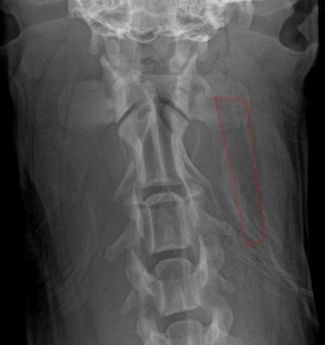

• КТ и МРТ. Оснащение ветеринарной больницы позволяет проводить диагностику плотных структур и комплексных систем организма с высокой детализацией.